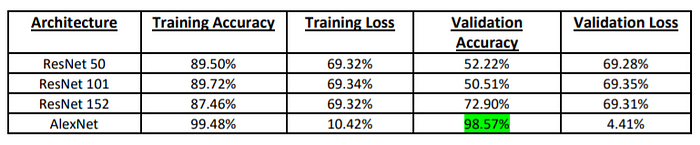

5. The above images where then classified using four distinct architectures viz. Resnet50, Resnet101, Resnet152 and AlexNet. The logic that is used in the classification is that in case when blood is actually flowing through the vessel a luminescent spot is picked up by the algorithm whereas in case when the blood is not flowing or stalled a black spot can be observed. So when we are looking at images of a non Alzheimer individual the frequency of these bright luminescent spots would be higher as compared to the black spots and vice versa for an Alzheimer infected person. Whichever algorithm is able to best pick up this difference will give us the highest accuracy

Result

AlexNet was seen to give the best performance with a huge accuracy of 98.57%. Not only the accuracy is high, but the losses are low as well. The AlexNet model helped hugely in predicting accurately a person affected by Alzheimer’s.